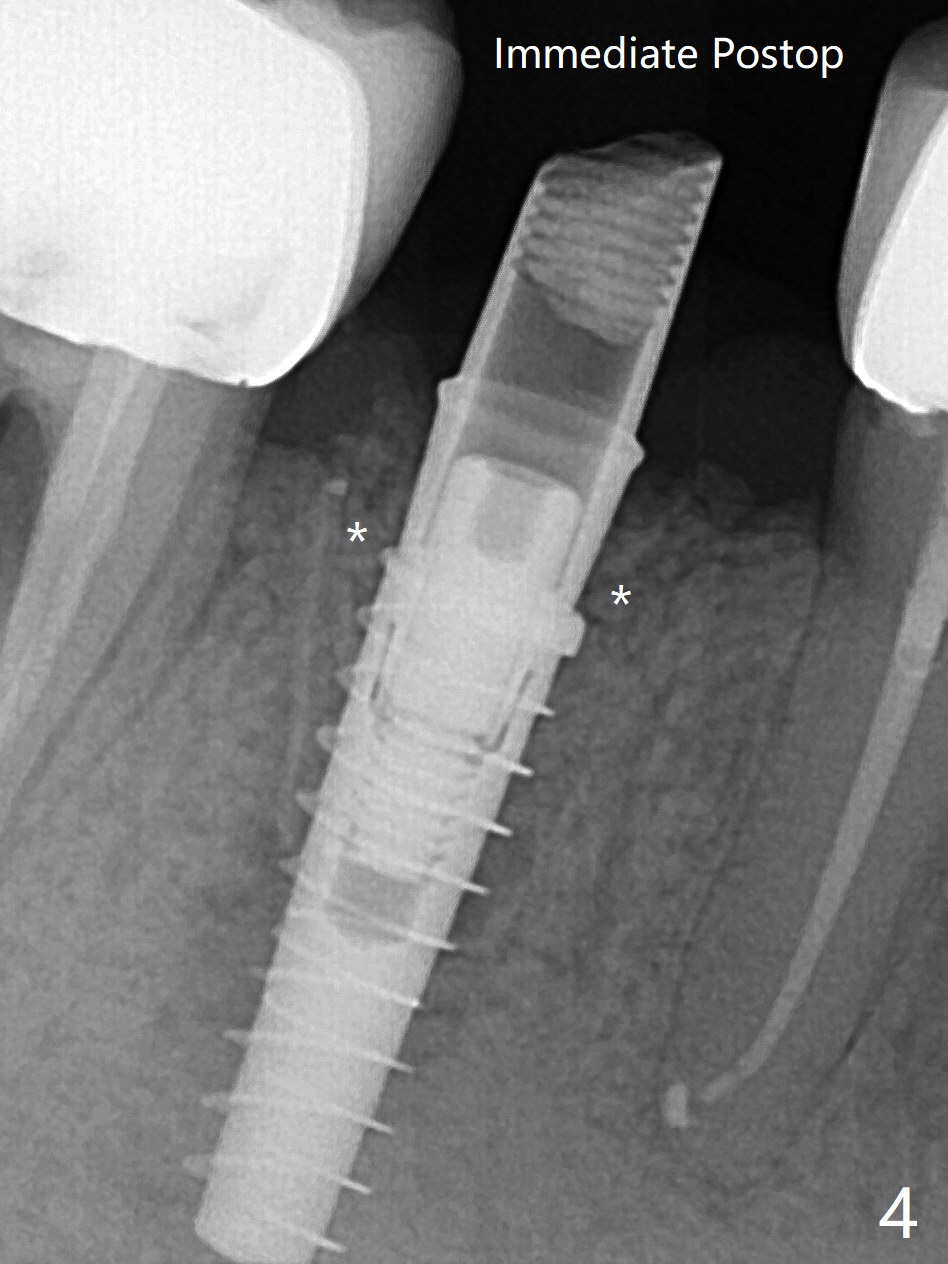

为了准确,这个病例徒手种植需要拍摄8张X光片(这里仅显示其中4张,图一至四),如果采纳导板,2张足够了,而且不担忧神经损伤问题。